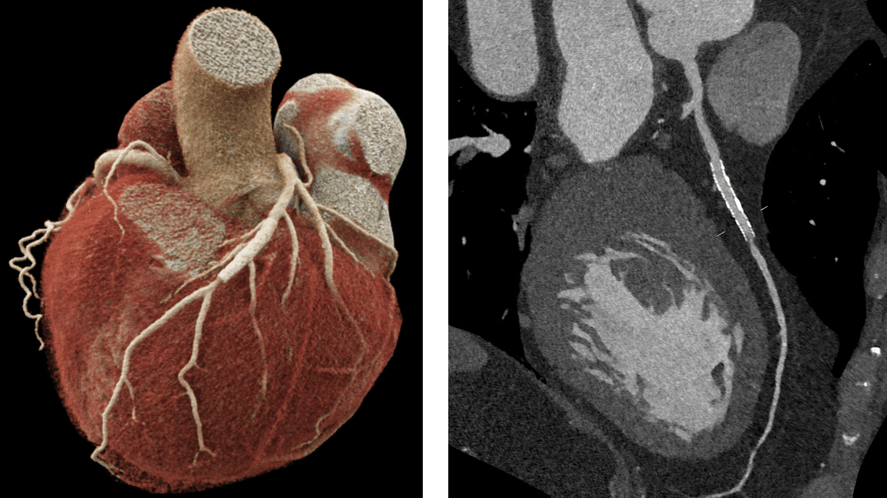

Cardiac CT

Stent patients can be assessed almost artifact-free. The lumen before, inside, and after the stent is clearly visible. Thanks to Flash mode, cardiac CT can be performed at very low doses (approx. DLP 50) with image quality that clearly surpasses the previous system.

Figure 3: Modern cardiac imaging using photon-counting CT: Comparison between VRT (left) for anatomical overview and MPR slice (right).